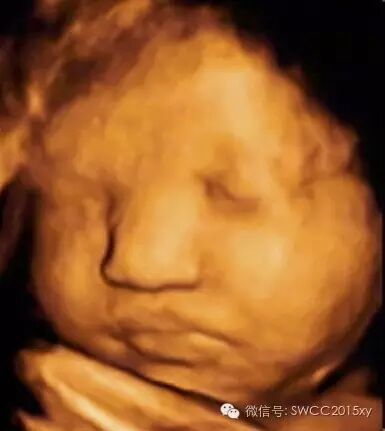

第六点,带环怀孕后对胎儿有影响吗?   带环妊娠中宫外孕的发生率为4%左右,环(节育器)是安放在宫腔里的,胎儿的生长是在羊膜囊内的。早期孕囊在宫腔内做床的时候,他较小在宫腔内和环有一定距离,是不同的二个个体,分别在子宫宫腔内的不同位置。随着胎儿的长大他们之间的距离就越近,甚至胎儿生长占据大量空间就会把环(节育器)挤在一边,但是他们中间还是有羊膜囊隔开。不管胎儿长多大他和环都会有羊膜囊隔开,因此根据“

全或无”的理论,环在宫腔内不影响胎儿的发育,在我们的临床工作中很多孕妇都顺利的生下了小宝贝并取出了环。